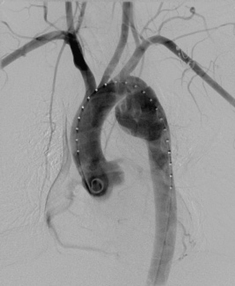

image

Figure 32.11 Male. Age 38. RTA. Aortogram following intravenous injection of contrast medium. Rupture of the aorta at its isthmus. Aortic isthmus: the junction of the aortic arch and the descending aorta.